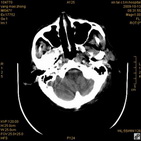

病人杨XX,男,青云街道办事处路踏泉村,住院号51666,CT号:104770。病人因“高血压脑出血”在新泰市人民医院住院治疗5天,治疗效果不佳转入我院,复查CT示左基底节血肿,病人昏迷状态,给予血肿清除术,术后2天复查CT,血肿完全清除,病人恢复好,治疗效果满意。附病人术前术后CT片资料如下。

术后46小时复查CT

术后46小时复查1 术后46小时复查2 术后46小时复查3 术后46小时复查4